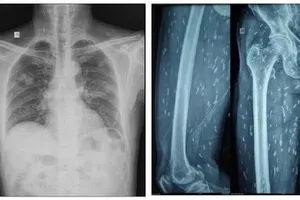

Nam thanh niên 20 tuổi bị nhiễm sán dây chó, giun lươn và sán lá gan lớn Y tế - Sức khỏe 20/02/2025 20:05